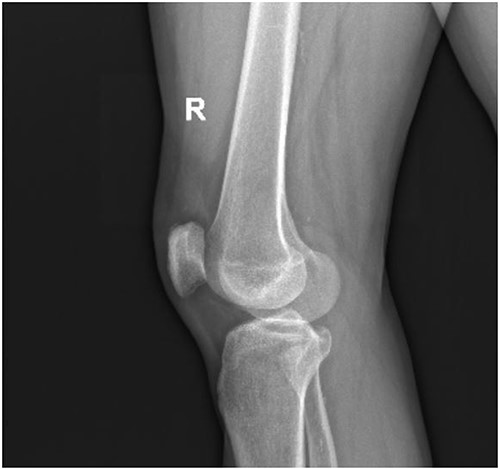

A 62-year-old male presented to emergency department of our hospital with complaints of low back pain and decrease range of motion of the right knee due to a fall from standing height. The patient was unable to weight bear and to perform a straight leg raise. His past medical history revealed no significant records. Clinical examination revealed a low back pain without neurological deficit and tenderness at right knee with a palpable defect proximal to the superior pole of the patella. Passive flexion of injured knee was measured as 110° and passive extension was full. Routine laboratory tests including white blood cells (WBC) count, erythrocyte sedimentation rate (ESR), c-reactive protein (CRP), liver and renal function were within normal ranges. The X-rays of the knee were normal without findings of patella baja and osseous pathology (Fig. 1), but the X-rays of the pelvis revealed bilateral sacroiliac arthritis. Based on this finding, further laboratory evaluation revealed a positive HLA-B27. An ultrasound scan performed externally showed a hypoechoic gap and quadriceps complete tear was noted. Magnetic resonance imaging (MRI) confirmed the findings seen on ultrasound with the difference that the rectus femoris (RF) was intact and there was a rupture of intermedius tendon (IT) combined with a partial rupture of vastus medialis. MRI sequences, especially T2W images revealed an intramuscular hematoma and discontinuity in the vastus IT (Figs 2 and 3). A small fluid filled defect, in the vastus intermedius just proximal to the insertion of quadriceps into the patella was also detected. The rectus femoris and vastus lateralis (VL) were intact. The defect in vastus intermedius measured ⁓5 cm from its patellar insertion.

Lateral X-ray of the right knee without findings of patella baja and osseous pathology.